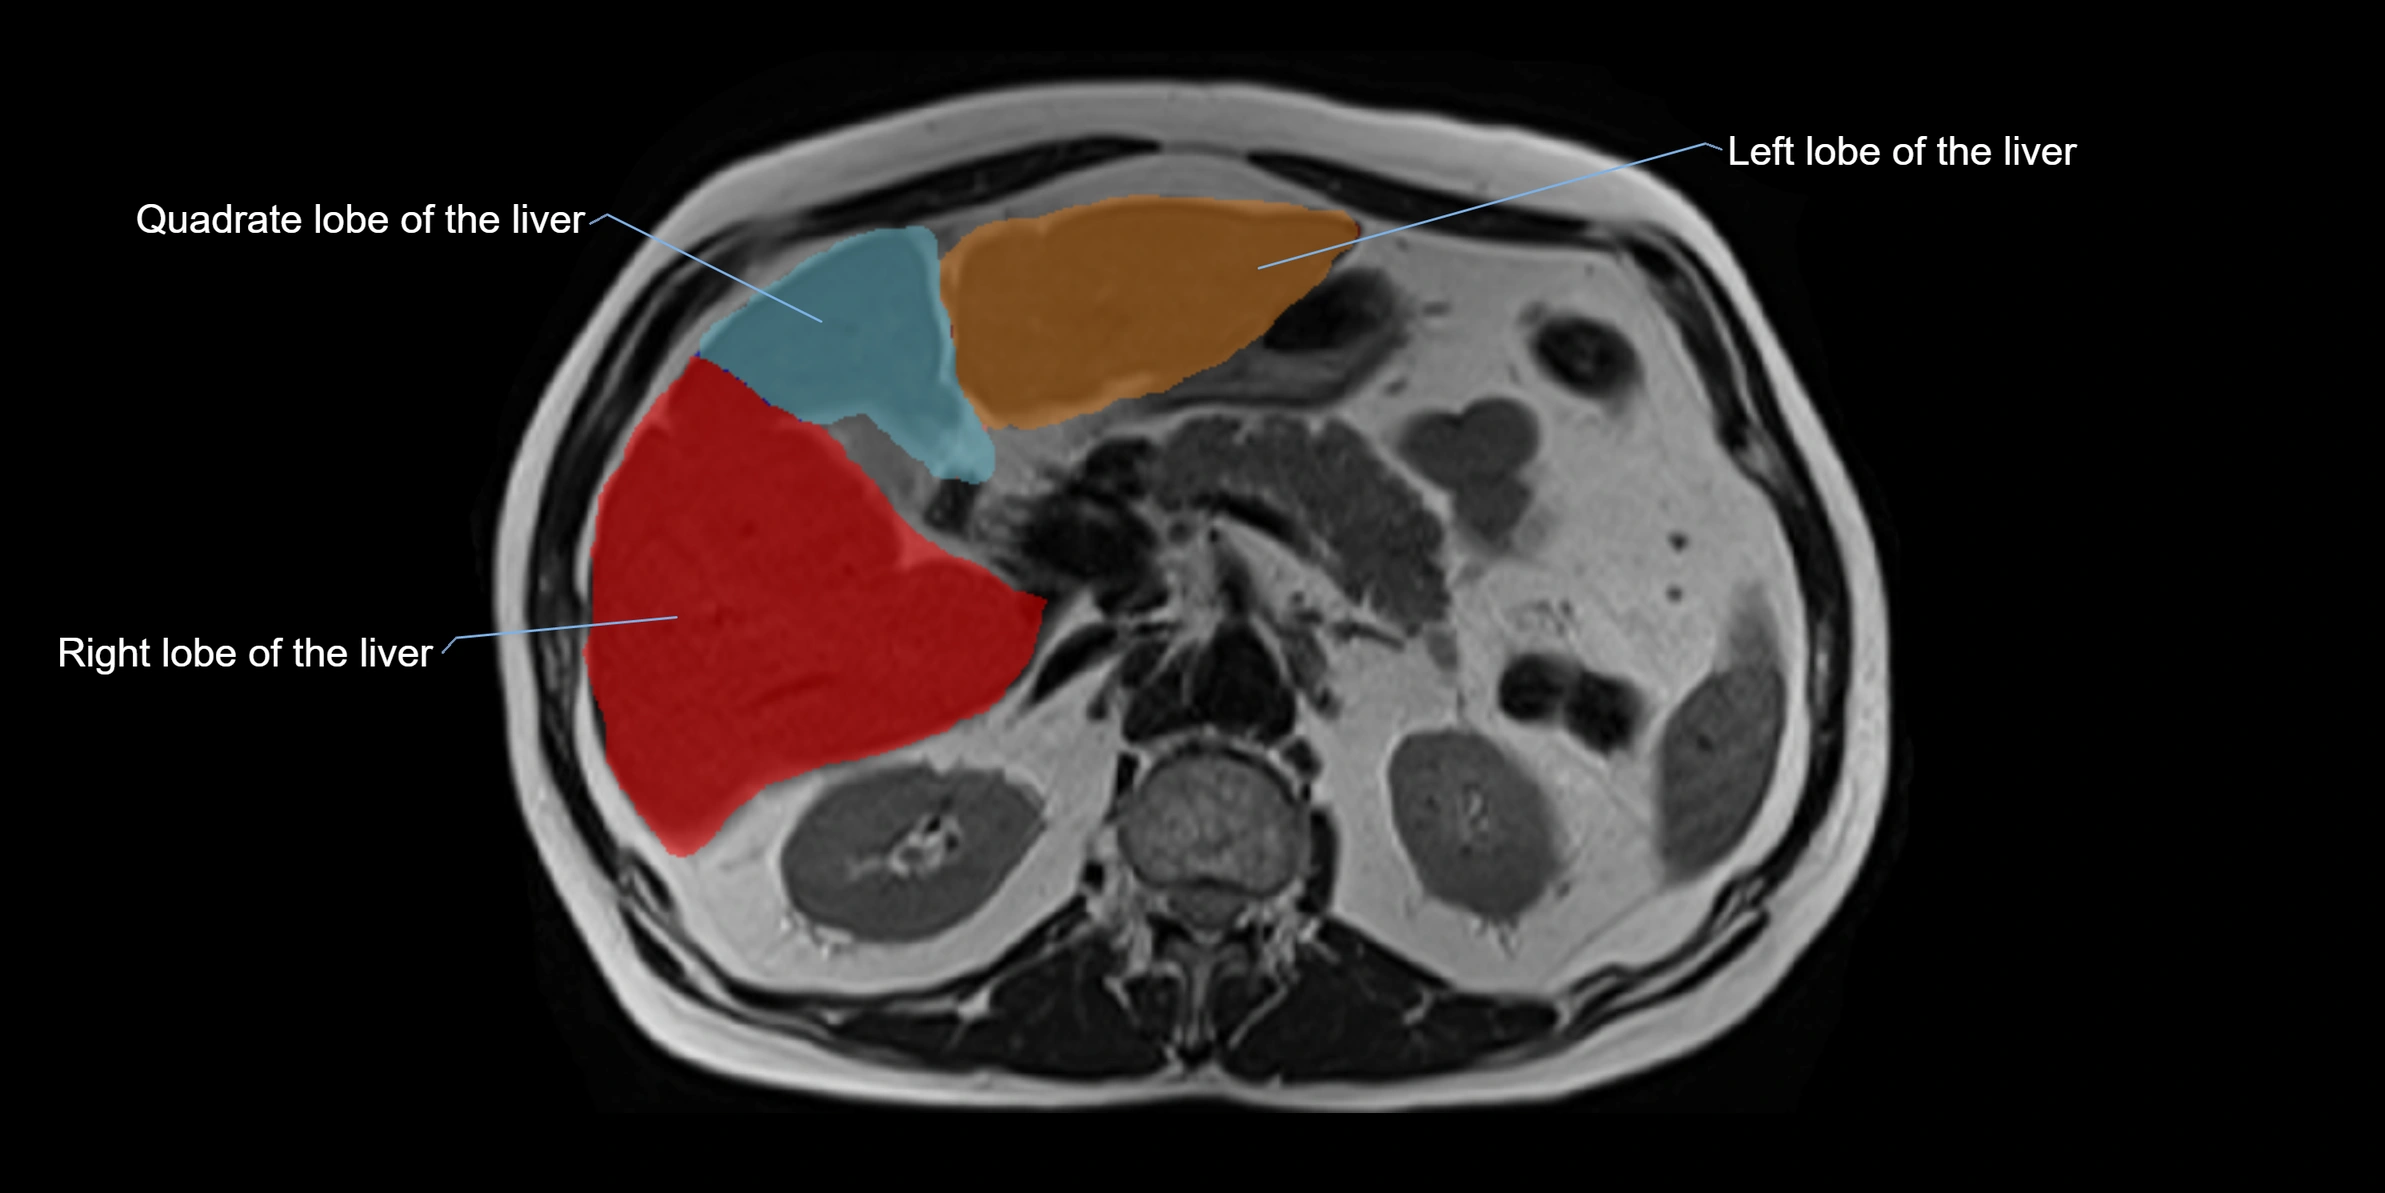

CT Image

image